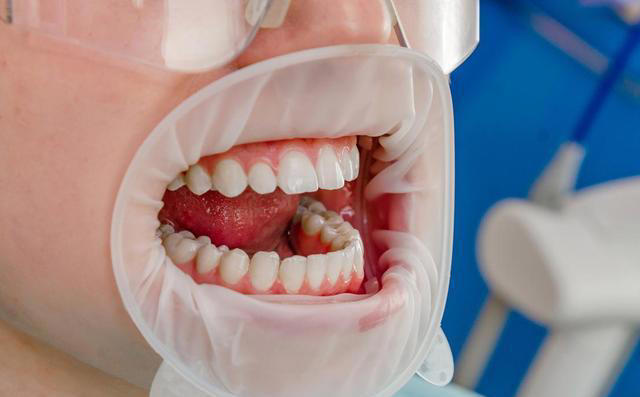

再有,刷牙时很多人都会用力过猛,认为这样可以刷得更干净。 其实,用力过猛不仅不会更有效地清洁牙齿,反而会加剧牙龈的磨损,甚至可能导致牙齿松动。刷牙时我们应该保持适当的力度,牙刷与牙齿之间的角度大约为45度,用轻柔的画圈动作刷牙,这样可以有效清洁牙齿,又不会对牙龈造成伤害。 此外,很多人刷牙时忽略了舌头的清洁。 舌头上有大量的细菌,如果不及时清洁,很容易导致口气不清新,甚至可能引发口腔疾病。对于老年人来说,舌头上的细菌积聚可能会影响到整体口腔健康。 因此,医生建议,每次刷牙时,也要轻轻刷刷舌头,保持舌面的清洁。

还需要注意的是,很多人刷完牙后习惯直接漱口,认为这样可以更清爽。 但是,刷牙后立即漱口其实是错误的做法。牙膏中的氟化物在刷牙时能帮助保护牙齿,如果刷完牙后马上漱口,氟化物就会被冲走,失去保护牙齿的效果。 医生建议,刷完牙后最好等个几分钟再漱口,或者只用清水轻轻漱口,这样可以保持氟化物在牙齿上的效果,帮助预防蛀牙和牙齿敏感。

最后,很多人刷牙时习惯性地忽略了牙齿的内侧。很多人刷牙时,只关注外侧,觉得内侧没什么问题。 其实,牙齿的内侧同样需要清洁。尤其对于老年人,牙齿的内侧可能会积累更多的食物残渣和细菌,长时间不清洁,可能会导致蛀牙和牙龈炎症。因此,刷牙时一定要确保刷到牙齿的每个面,包括内侧和咬合面。